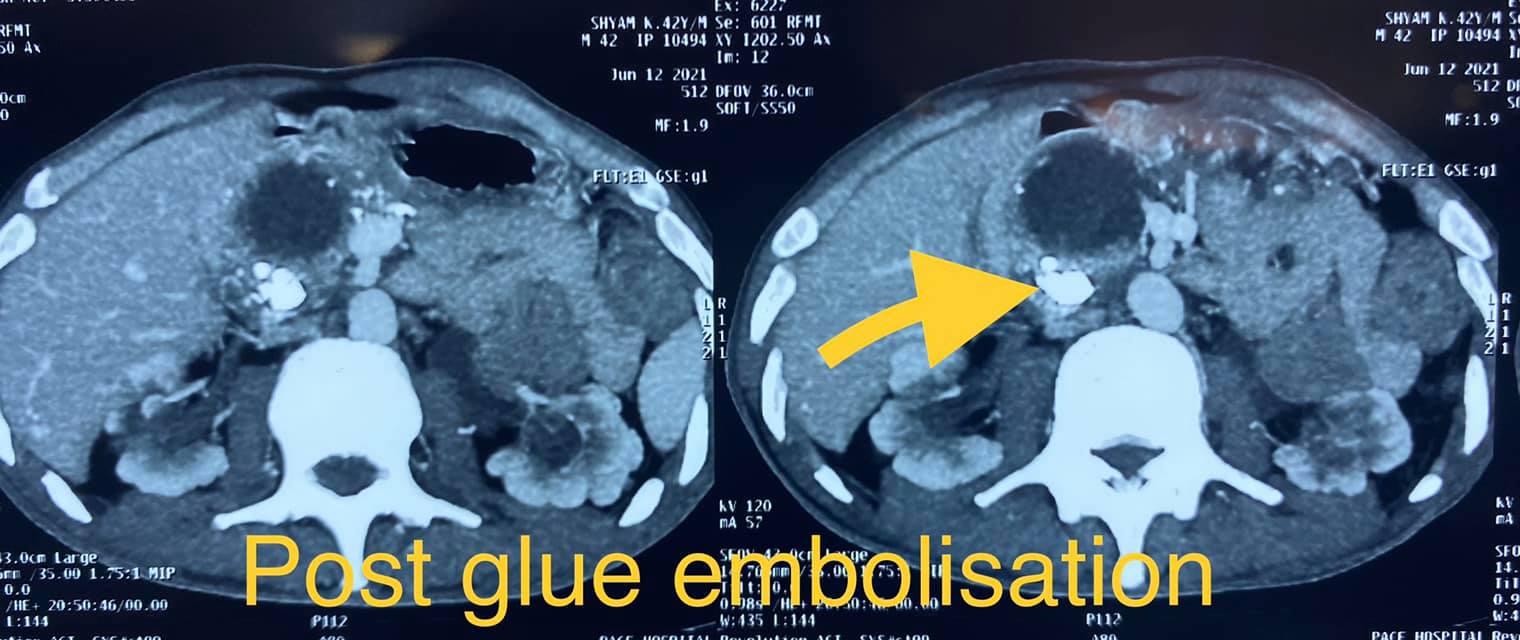

40 year old male with idiopathic chronic pancreatitis presented with intractable pain, sitophobia with severe weight loss (adult male weighs 29 Kg) and history of recurrent episodes of GI bleed. He also has CKD (cr1.7) related to neurogenic bladder. Patient was shifted to us in shock with HB 3 gm % and massive GI bleed. MRI and CT angio showed a large 6x5 cm Pseudoaneurysm in uncinate process of pancreas probably arising from inferior pancreaticoduordenal artery causing hemosuccus pancreas. In view of CKD we chose to tackle aneurysm by direct glue embolisation of aneurysm sac to avoid the high volume contrast of conventional angio (image) Pt was put on NJ feeds in view of severe malnutrition secondary to intractable pain and sitophobia. Post embolisation 2 months later he came back with weight gain of 8 kg and a stable Hb%. His Repeated CT scan showed a persistent intrapancreatic head cyst with dilated pd in body and tail. The aneurysm cavity filled with glue cast has shrunk to almost one fifth the initial size. In view of large duct disease with Pseudoaneurysm we decided to go ahead with a whipple pancreaticoduodenectomy. The post op specimen shows the intrapancreatic cyst and the glue cast of the aneurysm (yellow arrow). His recovery was uneventful and is completely pain free post procedure.